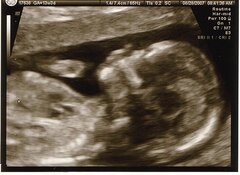

In augustus en september onderzoekt het Comité van de Verenigde Naties voor de rechten van personen met een handicap (CRPD) de situatie van personen met een handicap en hun rechten in België. Een van de kwesties die aan de orde kunnen worden gesteld zijn de implicaties van systematische screening op trisomie 21 tijdens de zwangerschap.

Op het vlak van bio-ethiek valt nog af te wachten of de CRPD de sociale en ethische implicaties zal onderzoeken van de veralgemeende prenatale screening op Downsyndroom in België, met behulp van de NIP-test. Deze niet-invasieve bloedtest wordt routinematig aangeboden aan zwangere vrouwen en wordt volledig vergoed door de Belgische staat. Er is geen officiële campagne om vrouwen en koppels aan te moedigen het kind te houden of, omgekeerd, een abortus te laten uitvoeren als er trisomie wordt vastgesteld (vooral voor trisomie 21, de meest voorkomende). Hoewel de zorgverleners verondersteld worden de keuze over te laten aan koppels die met deze mededeling geconfronteerd worden, worden in België toch meer dan 95% van de zwangerschappen afgebroken in geval van een diagnose van trisomie 21 (zie IEB 25/02/2021).